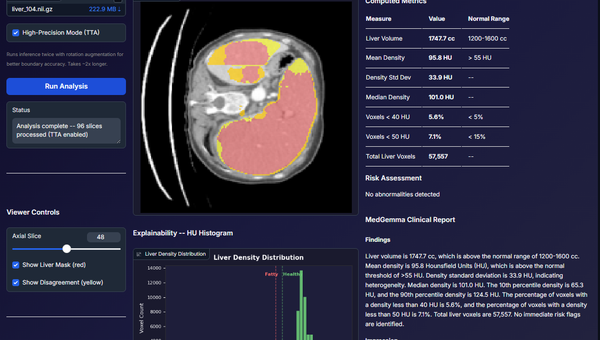

This was my first experience working with a large-scale 3D medical imaging dataset. The MSD Task03 Liver dataset is over 25GB, and training a full 3D model required designing a strong backend pipeline for data preprocessing, batching, and sliding-window inference. Training the model for ~160 epochs on my local RTX 3060 (12GB), and the system achieved a 95.6% Dice score. SwinUNETR captures long-range anatomical dependencies better than CNNs. What the system does: 1. Reads and processes full 3D abdominal CT volumes 2. Standardizes orientation (RAS), voxel spacing, intensity ranges, and crops foreground 3. Uses a 3D Vision Transformer (SwinUNETR) for segmentation 4. Handles inference using MONAI’s sliding-window engine and produces accurate 3D liver masks that can be downloaded as NIfTI files What I built: 1. A fully modular preprocessing pipeline (orientation, cropping, resizing) 2. An optimized training loop with Dice loss, mixed precision, checkpointing, and metric tracking 3. A complete evaluation script for volume-wise Dice scoring 4. A trained SwinUNETR model that generalizes well on held-out test CT volumes